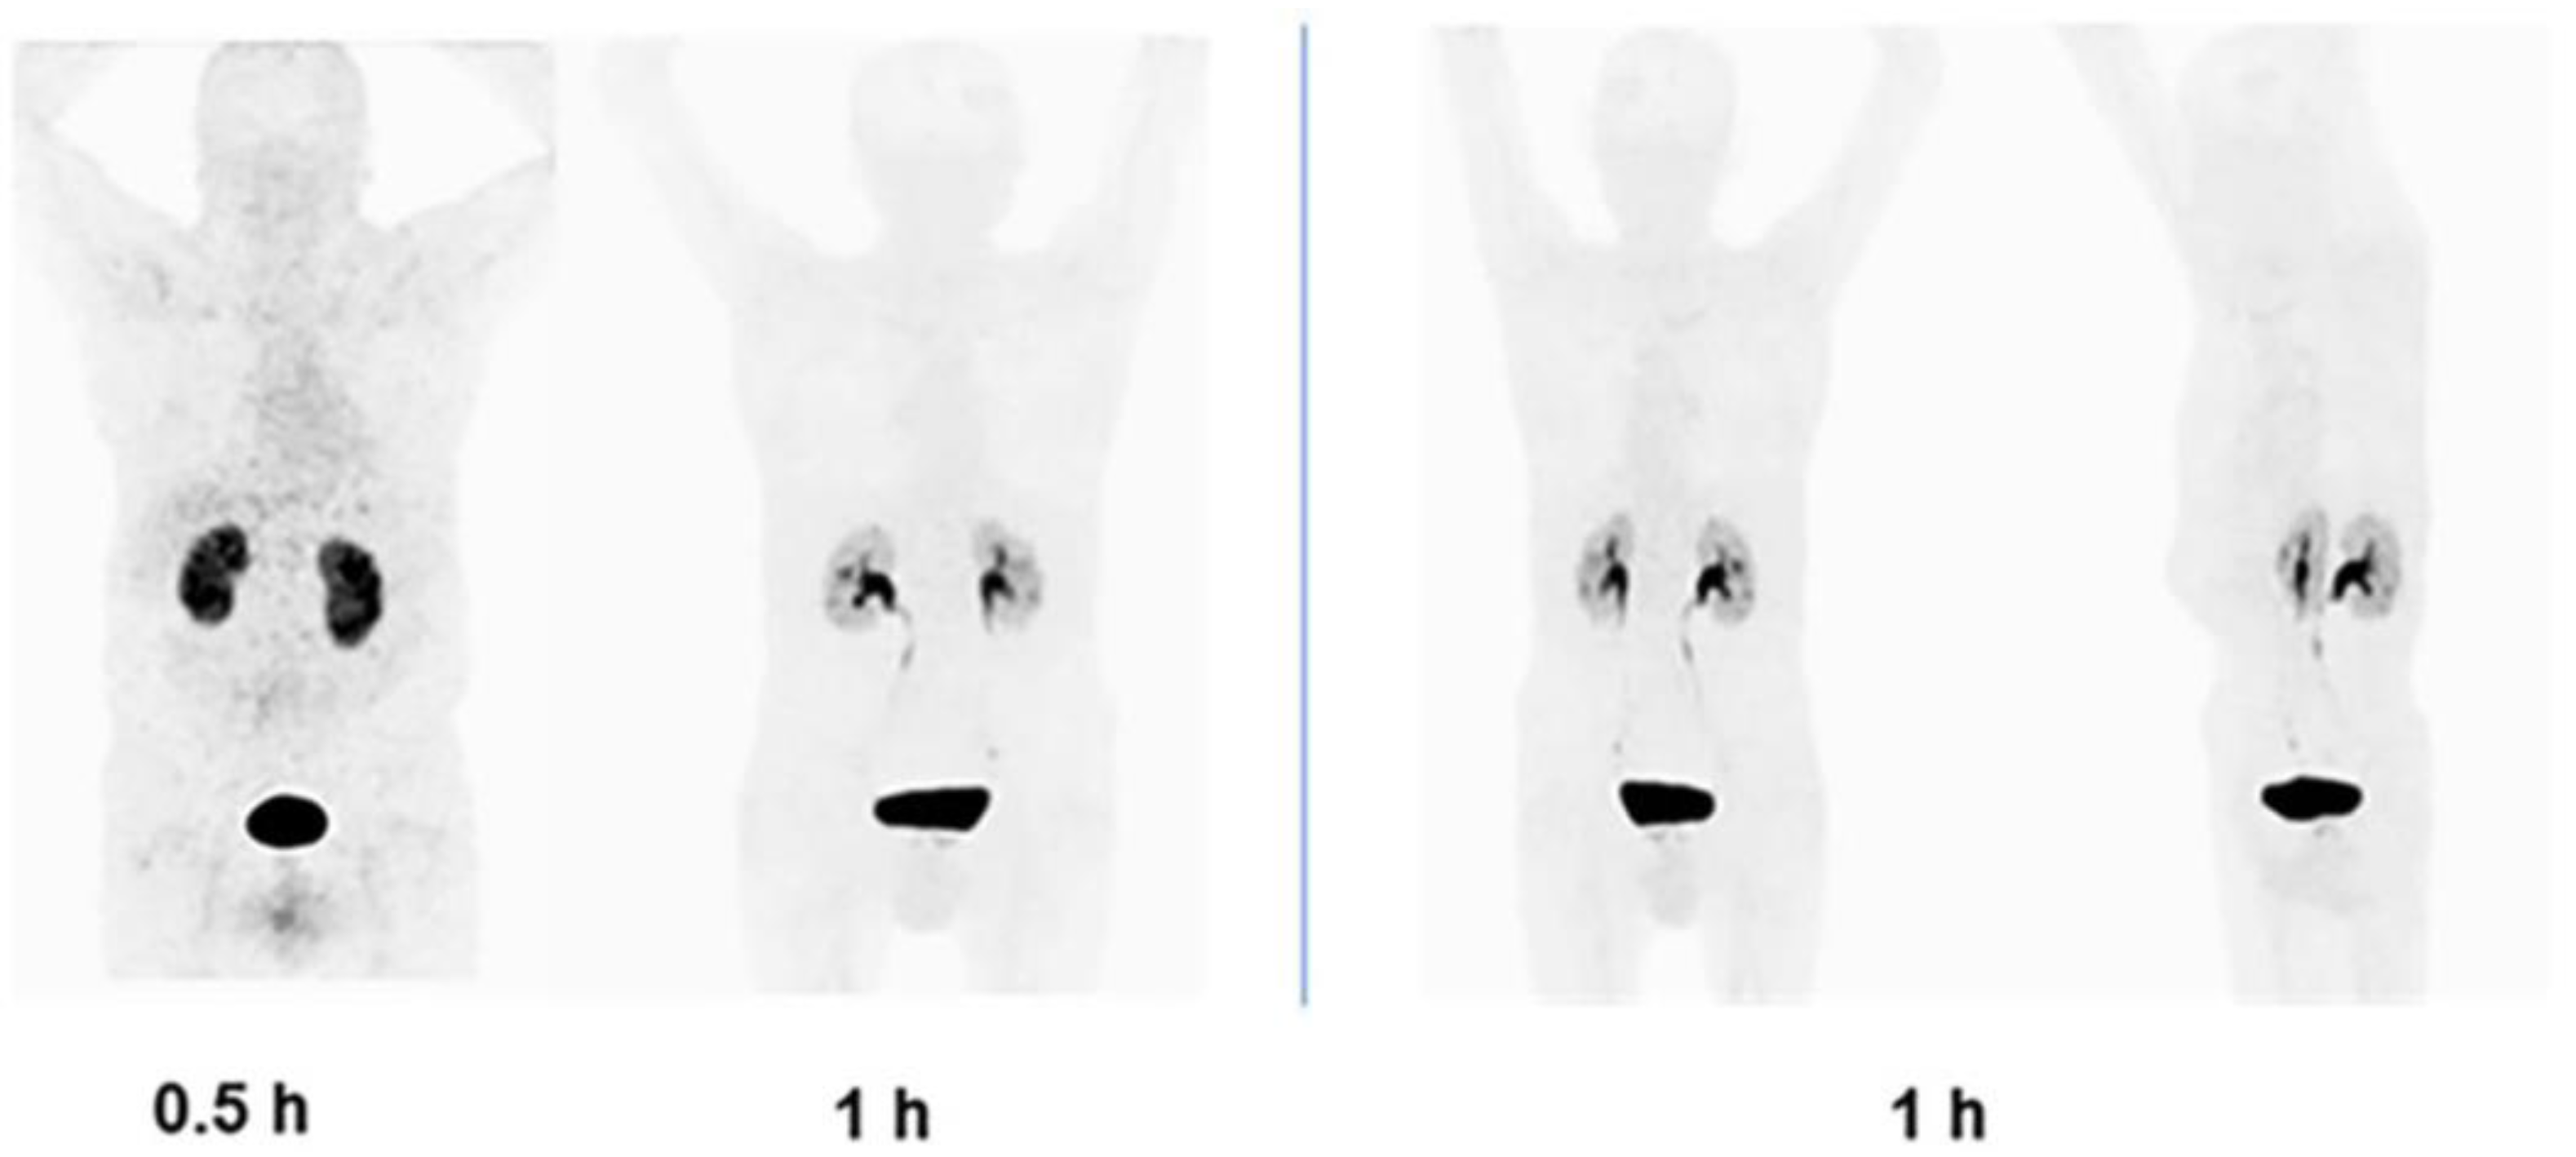

3.5. Clinical Imaging